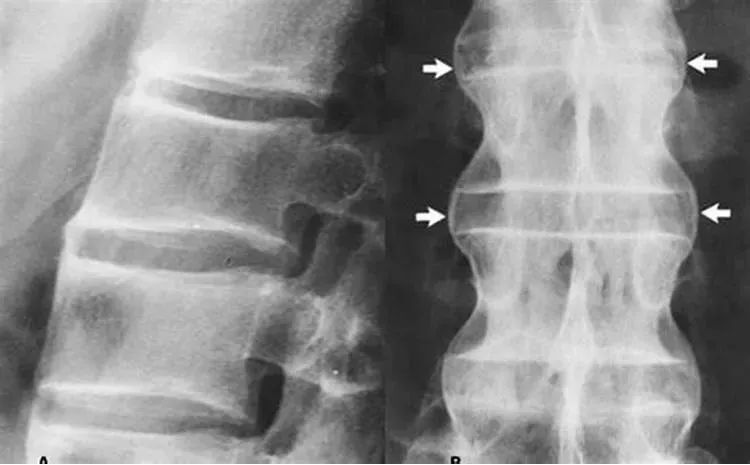

強直性脊柱炎的診斷

強直性脊柱炎的診斷主要基于患者的癥狀、體格檢查和影像學檢查,醫生可能會詢問患者的家族史和個人史,以了解可能的病因,血液檢查、X光、MRI等影像學檢查有助于確診強直性脊柱炎。